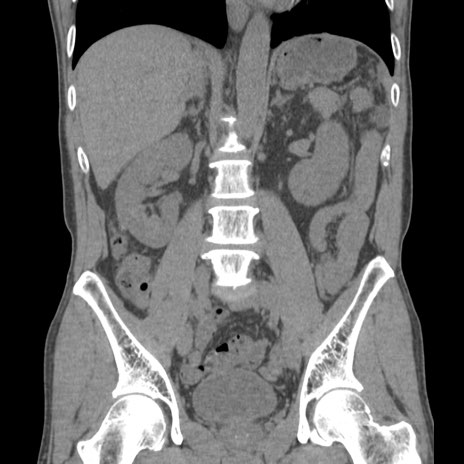

症例56 CT(冠状断像)

横断像